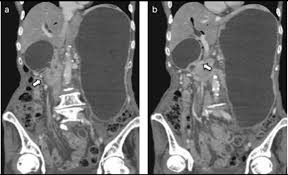

Zimmon Biliary Stents By Cook Inc Grayline Medical - Abdominal pain and jaundice appeared approximately 6 mo after the beginning of chemotherapy.

Tips And Tricks Of Double Balloon Endoscopic Retrograde Cholangiopancreatography With Video Hatanaka 2015 Journal Of Hepato Biliary Pancreatic Sciences Wiley Online Library - Stent patency in malignant lower biliary obstruction with chemotherapy.